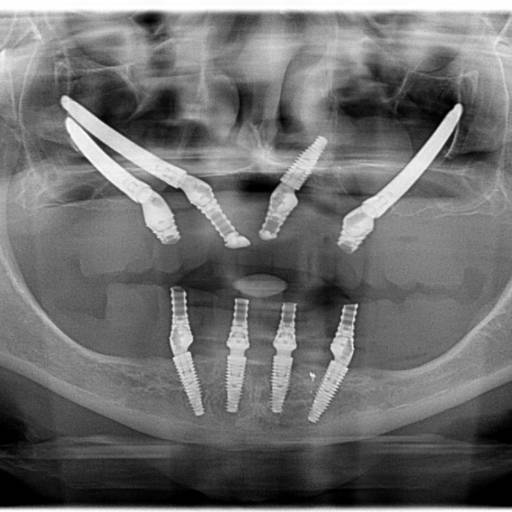

Na Medeiros Odontologia, oferecemos uma variedade de serviços que cobrem todas as necessidades odontológicas, desde cuidados preventivos até tratamentos complexos. Nosso principal destaque é o Implante Zigomático, ideal para pacientes com perda óssea significativa. Outros serviços incluem:

- Protocolo All On 4: Uma técnica avançada para quem busca próteses dentárias fixas.

Nosso principal diferencial é o atendimento altamente especializado e humanizado. Na Medeiros Odontologia, entendemos que cada paciente é único, e por isso nossos tratamentos são personalizados de acordo com as necessidades e expectativas de cada pessoa. Além disso, utilizamos as técnicas mais avançadas da odontologia moderna, como o L'PRF (enxerto), que acelera o processo de cicatrização e proporciona melhores resultados em procedimentos de implantes e cirurgias periodontais.